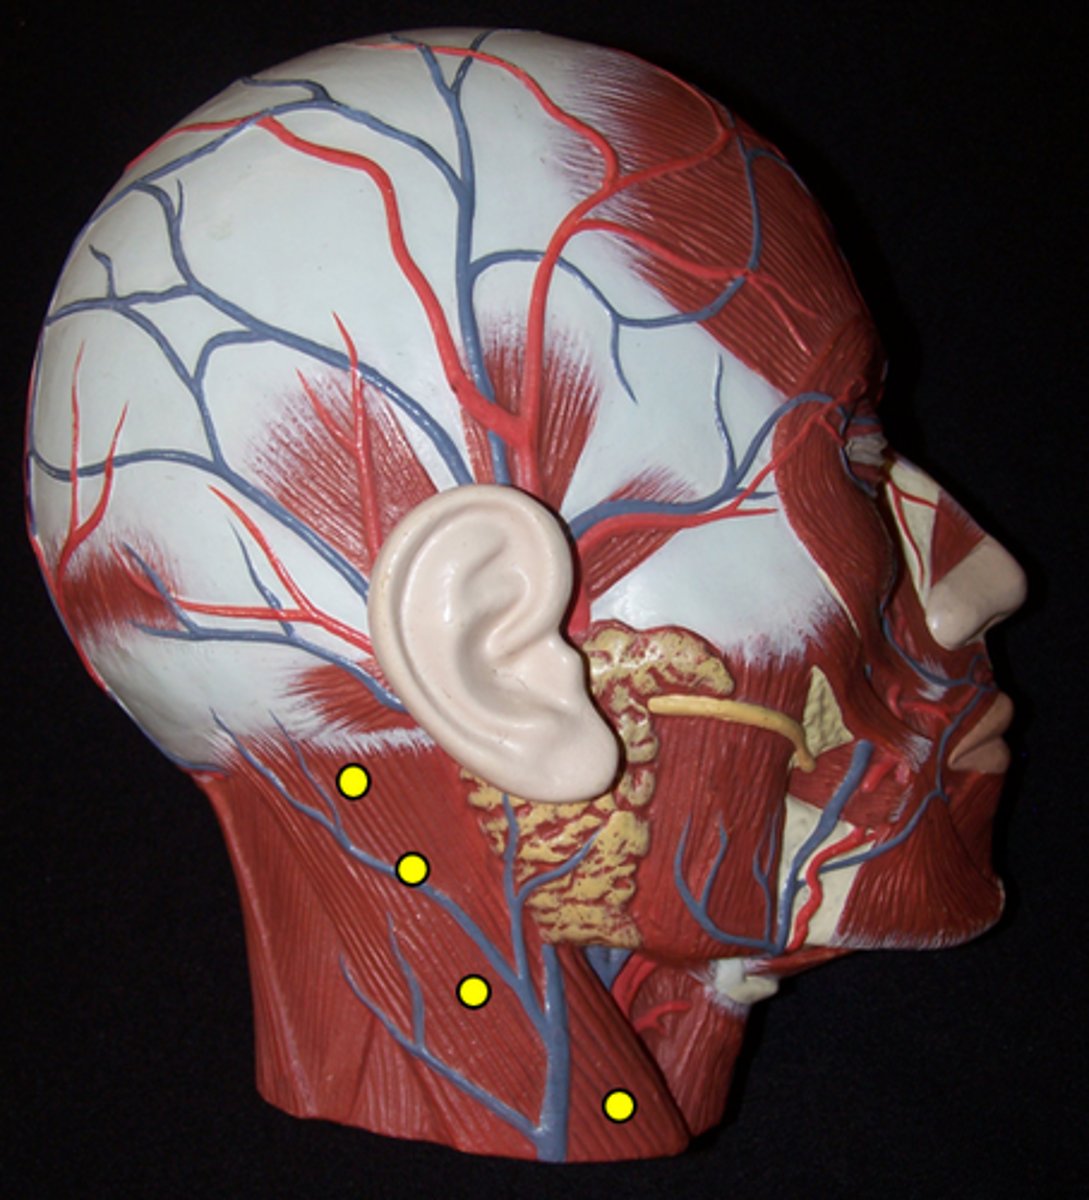

Frontal Belly of the Occipitofrontalis

Occipital Belly of the Occipitofrontalis

Epicranial Aponeurosis

Temporoparietalis

Corrugator Supercillii

Orbicularis Oculi

Procerus

Nasalis

Zygomaticus Major

Zygomaticus Minor

Orbicularis Oris

Levator Labii Superioris

Depressor Anguli Oris

Depressor Labii Inferioris

Mentalis

Buccinator

Platysma

Temporalis

Masseter

Medial Pterygoid

Lateral Pterygoid